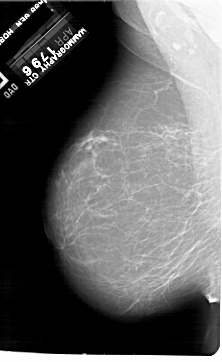

A_1923_1.LEFT_CC

LEFT_CC LINES 6361 PIXELS_PER_LINE 4066 BITS_PER_PIXEL 12 RESOLUTION 43.5 NON_OVERLAY